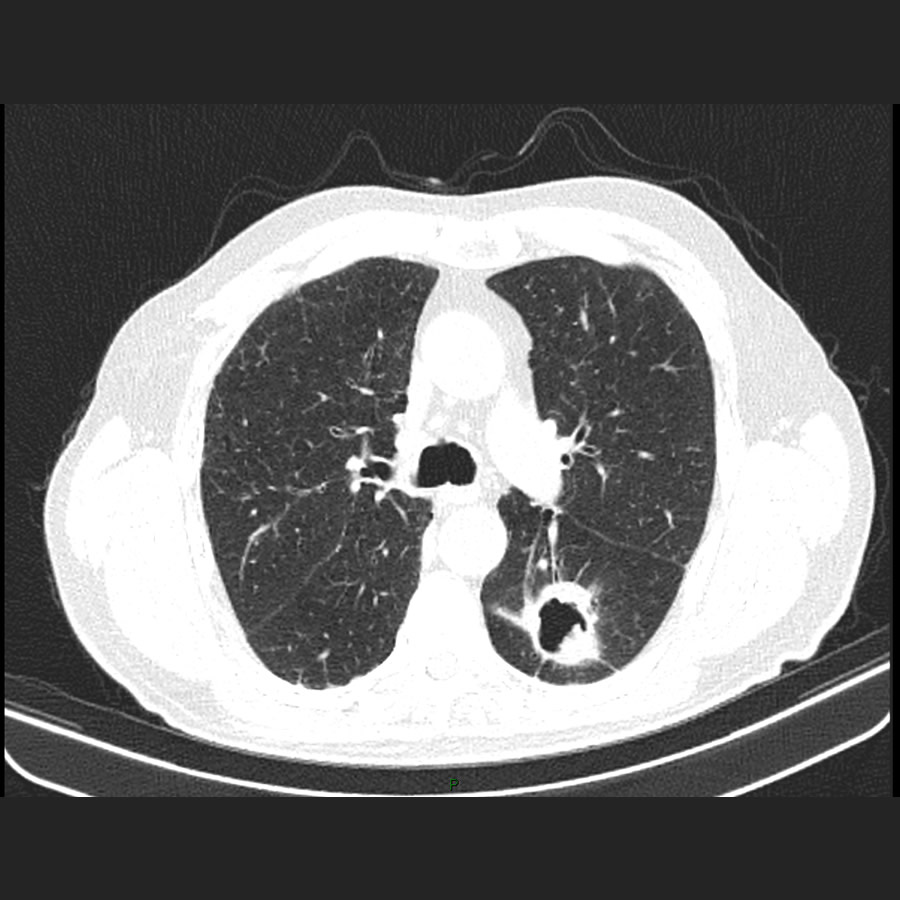

Paciente de sexo masculino de 75 años de edad, con app de IAM, ACV isquemico y adenocarcinoma de colon con tto qx, consulta con servicio de neurologia para control y dolor cervical